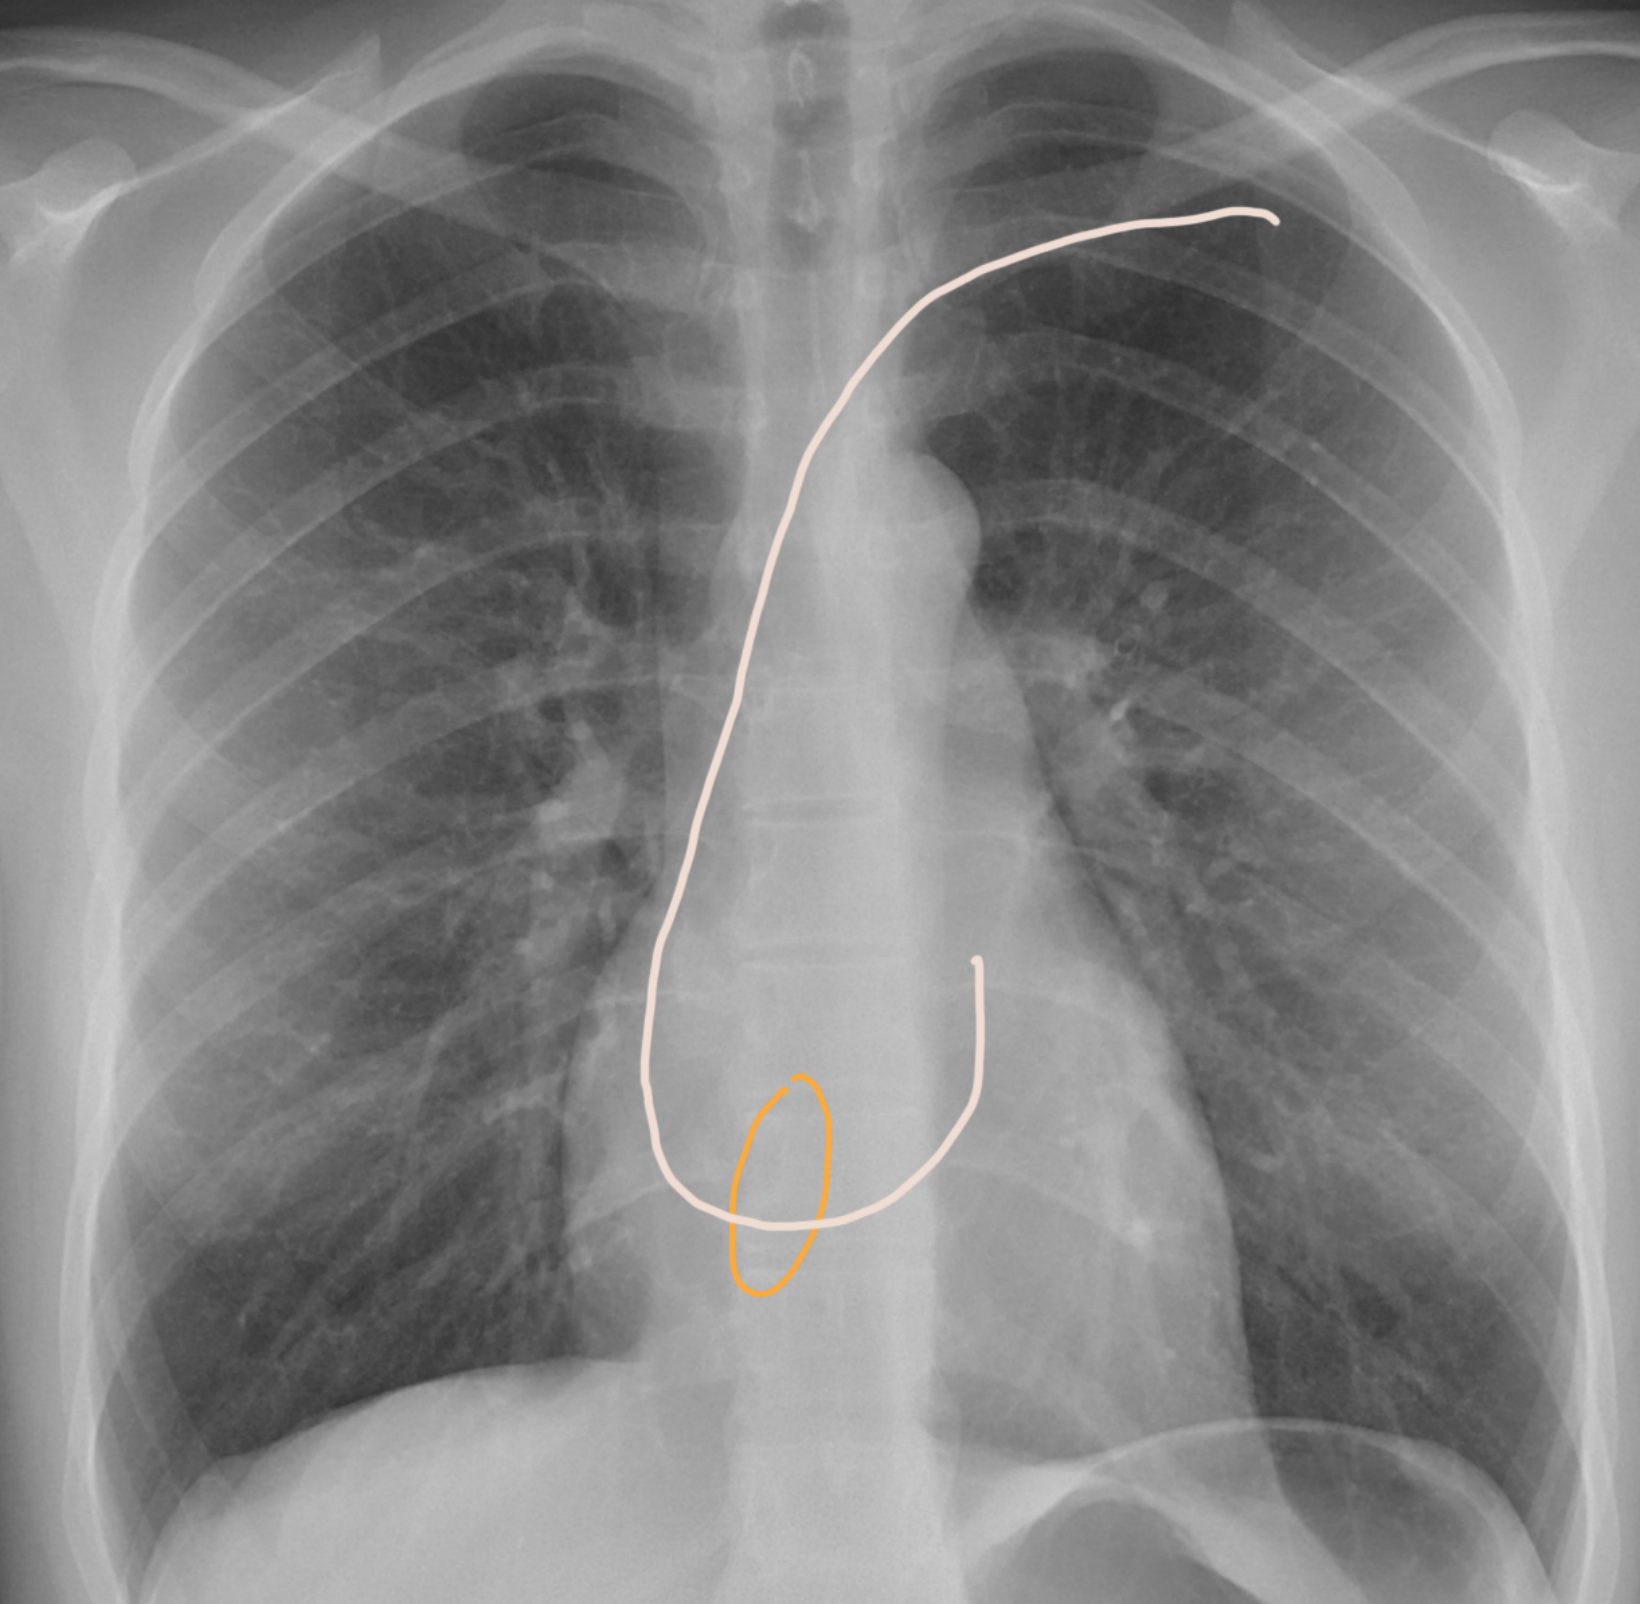

๐ŸŒ€ Step 22: Catch & screw the atrial lead! ๐ŸŽฏ

This part gets a bit more technical โ€” so hang on! ๐Ÿ’ช

๐Ÿ‘‰ Gently pull on the atrial lead until you โ€œcatchโ€ the RAA ๐ŸŽฃ.

Youโ€™ll notice the lead will start to horizontalize ๐Ÿ“ โ€” thatโ€™s your signal!

โœ… As soon as itโ€™s horizontal, itโ€™s time to screw it in ๐Ÿ”ฉ to secure the position.

Think of it like docking a spaceship ๐Ÿ›ธ: once it lines up perfectly, lock it down! ๐Ÿš€